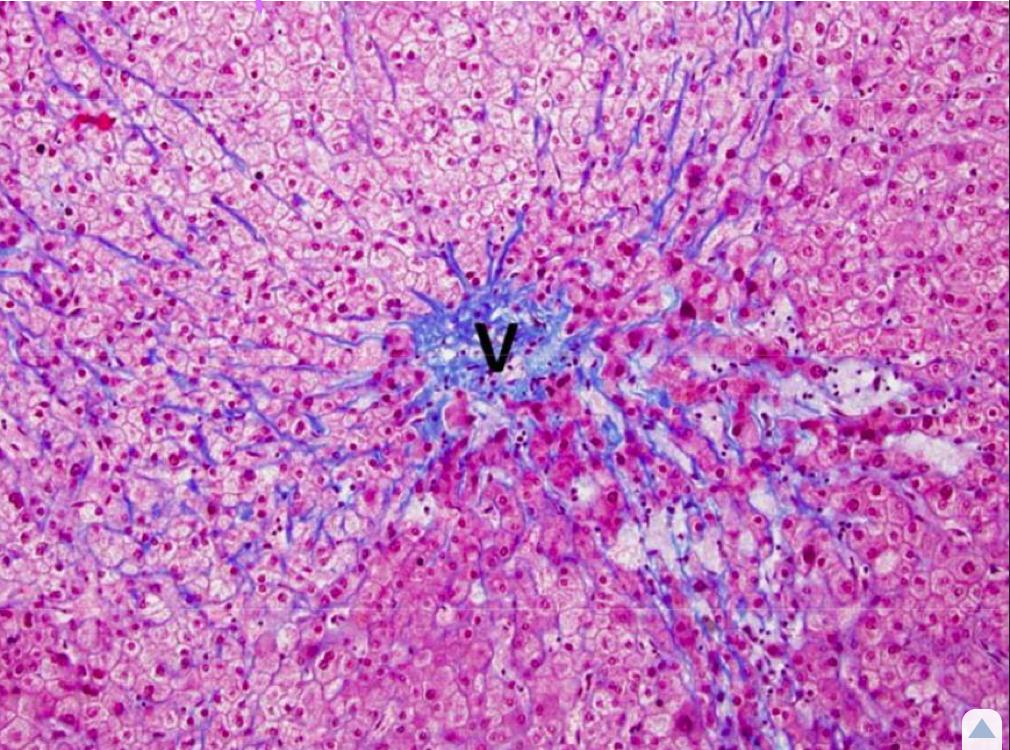

Histo on a liver specimen shows collagen deposition in the Space of Disse, caused by repeated injury. What is an implication of hepatic fibrosis?

Decreased blood filtration in the liver

*Bridging fibrosis is more likely to impair liver function byt segregating sections of the liver and cutting off blood supply.